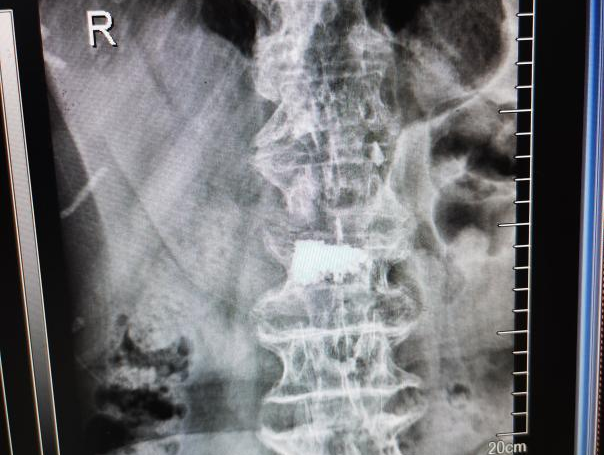

12月17日,贵州航天医院第88次晨读会由我院骨一科主任、副主任医师陈明勇作学术交流,他以“肱骨近端骨折并肩关节脱位的手术治疗”为题,全面讲解了该损伤的手术策略、术中血供保护理念及内侧支撑重建技术等内容,并通过多个典型病例图文资料分享了从损伤机制分析、手术步骤实施到术后随访评估的完整过程与关键细节,为临床处理此类复杂骨折提供了较为全面的技术参考,有助于在手术规划中结合个体情况开展针对性治疗。 贵州航天医院 骨科专家简介 陈明勇 骨一科主任,副主任医师 临床擅长:从事创伤骨科工作约20年,对骨缺损、骨不连、骨肿瘤、肢体畸形等的肢体矫形重建及功能重建,慢性化脓性骨髓炎的根治治疗、糖尿病足的保肢治疗、快速康复理念(ERAS)下的老年骨折的诊治,四肢复杂骨折的诊治,四肢骨折等微创手术治疗具有丰富的临床经验。 2004年毕业于遵义医学院临床专业,曾在中国人民解放军总医院、广西医科大学第一附属医院、上海第六人民医院骨科进修。中国中西医结合学会骨伤科专业委员会横向骨搬移治疗糖尿病足及微血管网再生学组首届委员,遵义市医学会创伤分会常务委员。 瞿 晖 骨科党支部书记,骨二科主任,副主任医师 临床擅长:对骨科的常见病、关节外科、脊柱外科及运动医学疾病的诊治具有丰富的临床经验,熟练掌握骨科手术操作技术。 毕业于遵义医学院临床医学系,2005年前往广州中山大学第一附院骨显微医学部进修学习,2011年前往成都华西医院进修学习,并多次在省内外学习骨科相关知识,是中华医学会骨科分会会员。 赵小锋 中共党员,骨二科副主任,副主任医师 临床擅长:从事骨科临床工作11年,对骨科常见病、多发病诊疗有较为丰富的临床经验,擅长脊柱相关疾病诊断及治疗,尤其是颈、腰、腿疼痛疾病诊断及治疗,擅长胸腰椎骨折微创经皮穿刺内固定术、经皮穿刺椎体成形术、经皮穿刺脊柱内镜下腰椎间盘摘除术、单纯开创腰椎间盘摘除术、腰椎滑脱复位椎间植骨椎融合内固定术、腰椎管狭窄减压融合内固定术及人工髋、膝关节置换术等。 2012年毕业于遵义医学院外科学专业硕士研究生,2019年参加“遵义市115医学人才精英计划”于上海交通大学第一附属医院培训学习,2023年于北京大学第三人民医院脊柱外科进修学习,曾获得遵义市优秀医师荣誉称号。 遵义市手外科第一届委员,遵义市医学会创伤分会第一届委员,遵义市医学会创伤分会第二届委员,贵州省康复医学会第三届脊柱脊髓专业会委员,遵义市医学会烧伤与整形外科学分会委员,发表论文5篇,其中国家级核心期刊1篇,SCI论文1篇,主持市级课题1项并结题,参与市级课题2项。 赵兴东 骨科主任医师 临床擅长:擅长骨科的常见病及各种创伤、四肢骨折创伤修复、骨感染、手足疾病的诊治和手足体表畸形的矫形整复,熟练掌握骨科四肢骨病及创伤的手术操作技术,尤其在四肢关节复杂性损伤、手足外伤、组织缺损创面、难治创面的皮瓣修复方面及平足、高弓足矫形方面及四肢慢性疼痛诊治、康复方面具有丰富的临床经验。 硕士研究生,毕业于遵义医学院临床外科系,2015年前往山东省立医院手足外科进修学习;遵义市医学分会创伤分会第一、二届委员,遵义市手外科医学会第二委届员会常务委员;在省级及省级以上期刊发表文章9篇,参编著作2部,参与主持并完成市级课题1项,参与市级课题2项、省级课题1项。 张艳金 中共党员,骨科副主任医师 临床擅长:从事骨外科工作16年,对复合伤、多发伤的救治、四肢骨干骨折、关节周围骨折、骨肿瘤、骨髓炎等诊治具有丰富的临床经验。 中共党员,硕士研究生,2006年本科毕业于山西医科大学第二临床医学院,2011年研究生毕业于北京军区总医院;在“老年COPD患者合并髋部骨折的诊治”国际合作课题组研究两年,在老年髋部骨折的诊治方面具有丰富的经验,并发表论文6篇;主持遵义市级课题1项,承担遵义医科大学的临床教学工作,获得遵义医科大学优秀带教老师荣誉。编撰有《骨科疾病诊疗精粹》一书,开展2项新技术,编撰地方规范《务川自治县创伤骨科常见疾病诊疗规范》一书。 张俊凯 骨科副主任医师 临床擅长:从事骨科临床工作28年,对创伤骨折、骨感染、骨缺损、骨不连等外科诊治,四肢骨折的微创手术治疗,四肢复杂骨折(如关节内粉碎性骨折、多发骨折等)的损伤控制及手术治疗等具有丰富的临床经验。 1995年毕业于遵义医学院临床专业,2009年前往复旦大学附属医院骨科进修1年。 卢懿明 中共党员,骨科副主任医师 临床擅长:从事骨科工作18年,对创伤骨折、四肢骨折的微创手术治疗、四肢复杂骨折(如关节内粉碎性骨折、多发骨折等)的损伤控制及手术治疗,尤其是髋部骨折的PFNA等微创技术,踝关节骨折、膝关节周围骨折的Mipo微创技术等具有丰富的临床经验,开展了4项新技术,发明6项新型专利技术。 2005年毕业于遵义医学院临床专业,2017年,前往南方医科大学第三附属医院骨科进修半年,回院后运用Mipo技术对骨干骨折及干骺端骨折的治疗技术,同时积极开展骨盆骨折、髋臼骨折腹直肌外侧切口的应用;发表了多篇专业论文,经常参与省内外学术交流会授课,获得医院荣誉称号多个。 邬夏荣 骨科副主任医师 临床擅长:从事骨科工作16年,对四肢复杂骨折、骨肿瘤的诊治,尤其是足踝创伤、慢性踝关节损伤、平足症等诊疗具有丰富的临床经验。 2006年毕业于遵义医科大学临床医学专业,曾在陆军军医大学西南医院进修学习,发表多篇骨科学术论文。 余德怀 中共党员,骨科副主任医师 临床擅长:从事骨科工作10余年,对运动医学、骨关节、脊柱外科常见病、多发病的诊治具有丰富的临床经验。 硕士研究生,2011年毕业于遵义医学院临床医学专业,曾前往遵义医科大学附属医院运动医学专业进修学习;是贵州省医学会运动医学分会青年委员,西部关节镜联盟委员;发表多篇骨科学术论文。 冯 乾 骨科副主任医师 临床擅长:从事骨科工作近20年,熟练掌握骨科多发病及常见病的诊治,尤其对脊柱退变性疾病的诊断及治疗具有丰富的临床经验,主要研究脊柱微创相关治疗方式,能熟练开展椎间孔镜及UBE。 曾前往北京大学第三医院进修学习疼痛及椎间孔镜、首都医科大学友谊医院专业进修脊柱内镜;是贵州省康复医学会第三届脊柱脊髓专业委员会委员;发明专利3项、发表脊柱外科专业论文多篇。 贵州航天医院骨科简介 基本情况 贵州航天医院(原3417医院)骨科组建于1968年,前身是以创伤和断肢(断指)再植闻名于世的上海市第六人民医院骨科,中国断肢(断指)再植的奠基者、中科院院士陈仲伟等专家莅临科室指导医疗和教学,并在70年代开展了贵州省首例断肢(断指)再植手术。组建50余年来,诊治患者已逾百万,挽救了无数的伤病员,成为了保障遵义地区人民群众健康的重要支撑。 经过几代人的不懈努力,今天的骨科,已由创伤骨科发展至骨病、骨肿瘤、骨结核等领域,现有脊柱外科、关节外科、四肢创伤、手足外科四个亚专科,成为了集医疗、教学、科研于一体的综合学科,是贵州省临床重点专科、遵义市临床重点专科、遵义市骨科临床医学中心、遵义市基层骨科专科联盟理事长单位。 科室目前开放床位110张,共有医护人员50余人,副高级以上专家18人,硕士研究生15人。拥有一流骨科医疗设备多台,每年不定期选派优秀技术骨干到全国各大知名医学院校进修、学习、参观、交流,并邀请国内、国外知名专家教授来院进行交流、指导,通过不断引进国内外先进的诊疗技术,科室医疗技术水平稳步提升,为广大人民群众提供了优质的医疗服务。 专科特色 骨一科 (一)骨缺损、骨不连的肢体与功能重建 胫骨横向骨搬移技术治疗糖尿病足: (二)慢性骨髓炎的根治治疗 (三)肢体缺血性疾病如糖尿病足、脉管炎的保肢治疗 (四)皮瓣修复 (五)复杂创伤的治疗 (六)老年髋部骨折及小儿骨折快速手术 老年髋部骨折: 骨二科 (一)胸腰椎骨折微创经皮椎弓根螺钉固定术 (二)老年性骨质疏松性患者腰椎滑脱脊柱内固定术(骨水泥螺钉) (三)V形双通道脊柱内镜技术(VBE)腰椎融合术治疗腰椎退行性疾病 (四)老年性骨质疏松性骨折(PVP/PKP)术 (五)人工髋关节置换术 (六)双侧股骨头坏死人工全髋关节置换 (七)右侧全髋置换术后假体周围骨折翻修 (八)人工膝关节置换术 (九)人工膝关节假体松动翻修 (十)关节镜技术 传统手术切口 关节镜技术切口 诊疗范围 骨一科 1.四肢创伤、矫形。 2.手、足踝外科。 骨二科 end